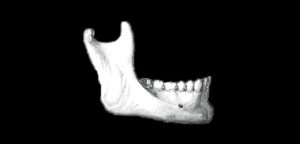

El conducto dentario inferior o canal mandibular se extiende desde el foramen mandibular por debajo de la espina de Spix al foramen mentoniano y dentro